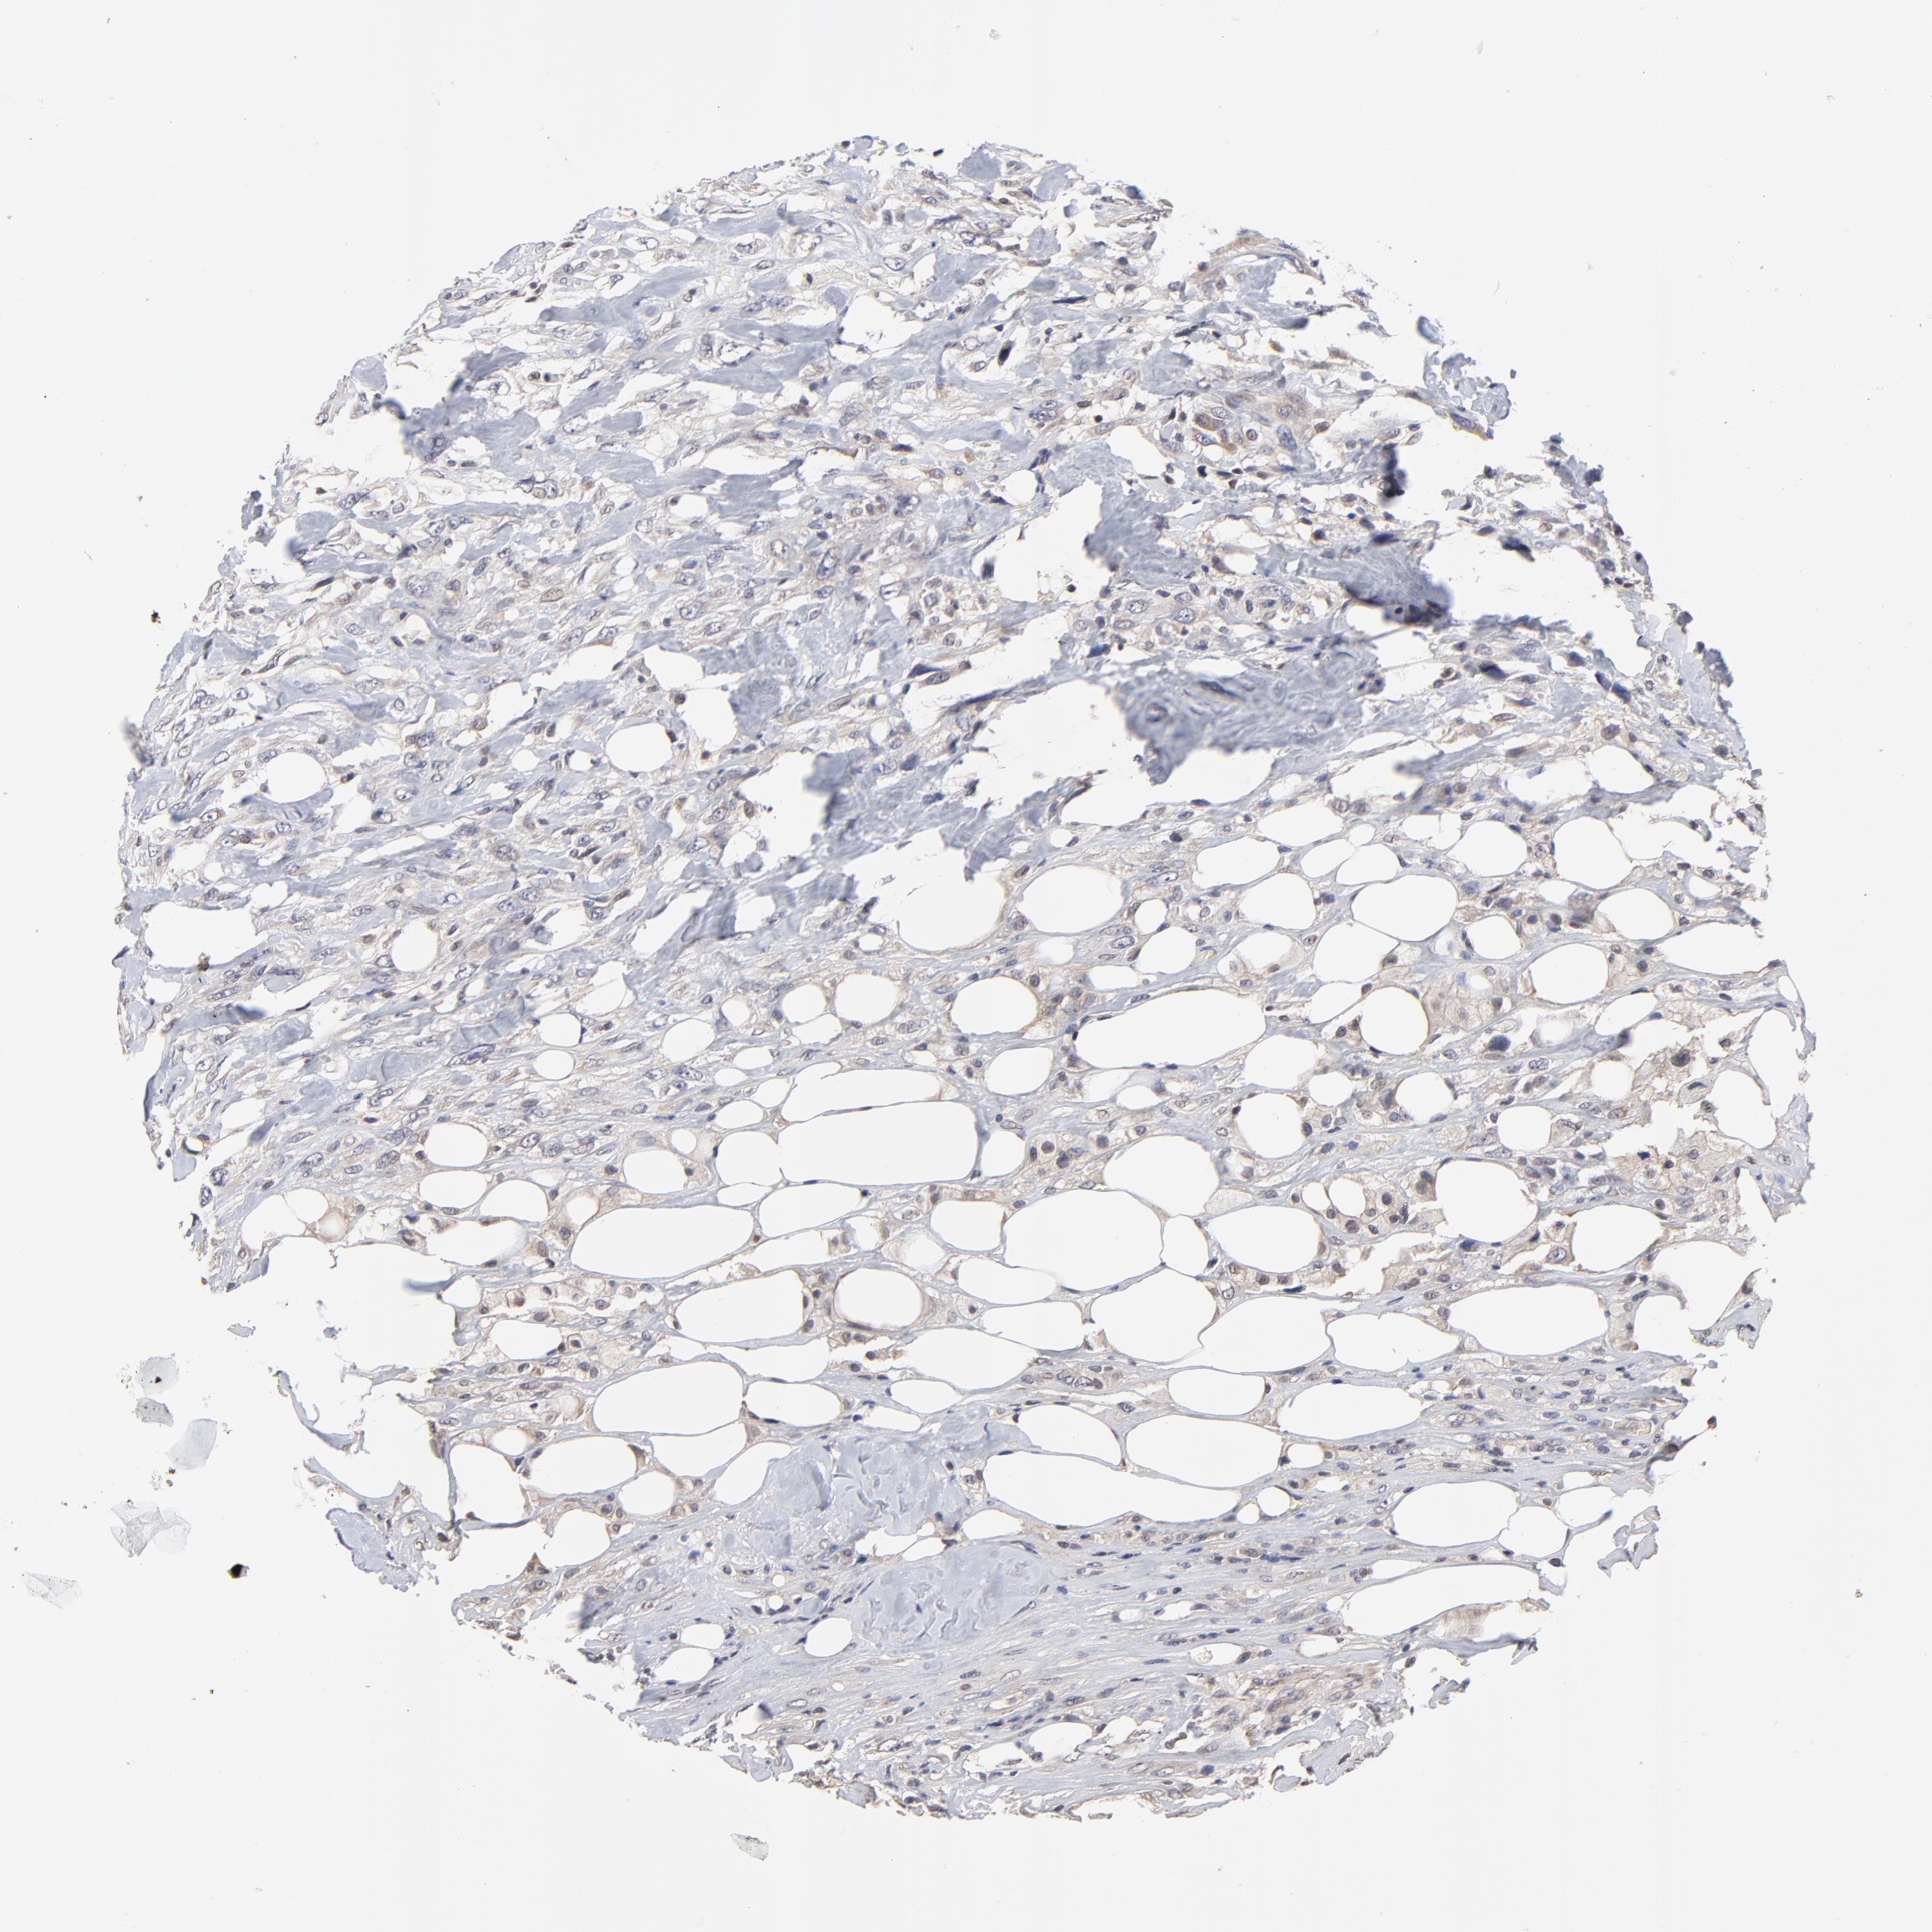

BRCA TCGA BRCA VALIDATION PROTEIN EXPRESSION

ANTIBODIES

AND

VALIDATION